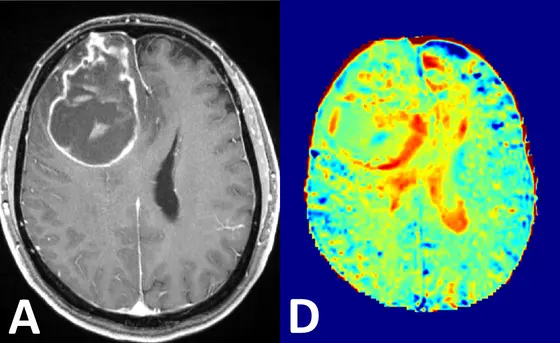

Visualization of brain cancer by conventional contrast agents (left) and by the novel glucose MRI method (right).

Scientists from the German Cancer Research Center (DKFZ), in collaboration with colleagues from Heidelberg University Hospital, have been able to visualize brain cancer using a novel MRI method. They use a simple sugar solution instead of conventional contrast agents, which can have side effects in the body.

In magnetic resonance imaging (MRI), contrast agents are used to enhance the imaging of tissue structures. While they enhance signals in blood vessels and in spaces between cells, they do not reach the interior of the cell. By contrast, glucose is taken up and then broken down in the body cells. Tumor cells are particularly hungry for glucose in order to feed their high energy needs. By observing glucose metabolism activity it may therefore be possible to identify solid tumors or very aggressively growing tumor areas. Radiologists and physicists from the German Cancer Research Center (Deutsches Krebsforschungszentrum, DKFZ) in Heidelberg have now succeeded in employing this novel type of imaging.

Conventional MRI is based on measuring the signals from protons in water. Since over 60 percent of our body is made up of water, this delivers a clear picture. Glucose is found at much lower levels in our body. In order to make it visible, the DKFZ researchers are therefore using an ultrahigh field scanner with 7 Tesla magnetic field strength and a special method to reinforce the glucose signal distinctly and selectively. This makes it possible to obtain sufficient signal strength in order to visualize changes in glucose levels in brain tissue after injection of a glucose solution.